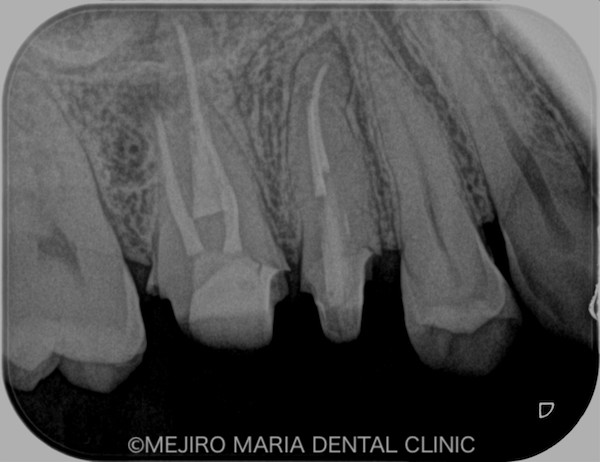

患者様は、「数年前に虫歯治療した歯の、根元が腫れた」という主訴で来院されました。かかりつけ医に相談したところ、痛くないのであれば様子を見るようにと指示されましたが、不安を抱いて当院へお越しになりました。

右上の歯を確認したとろ、当該部位にはフィステル(瘻孔)が確認でき、フィステルより造影してみると、右上6番の歯の根尖部付近から、排膿されていることがわかりました(写真の赤矢印)。フィステル以外に痛みなどの所見は見当たらないものの、「根尖性歯周炎」と診断し、治療を開始しました。